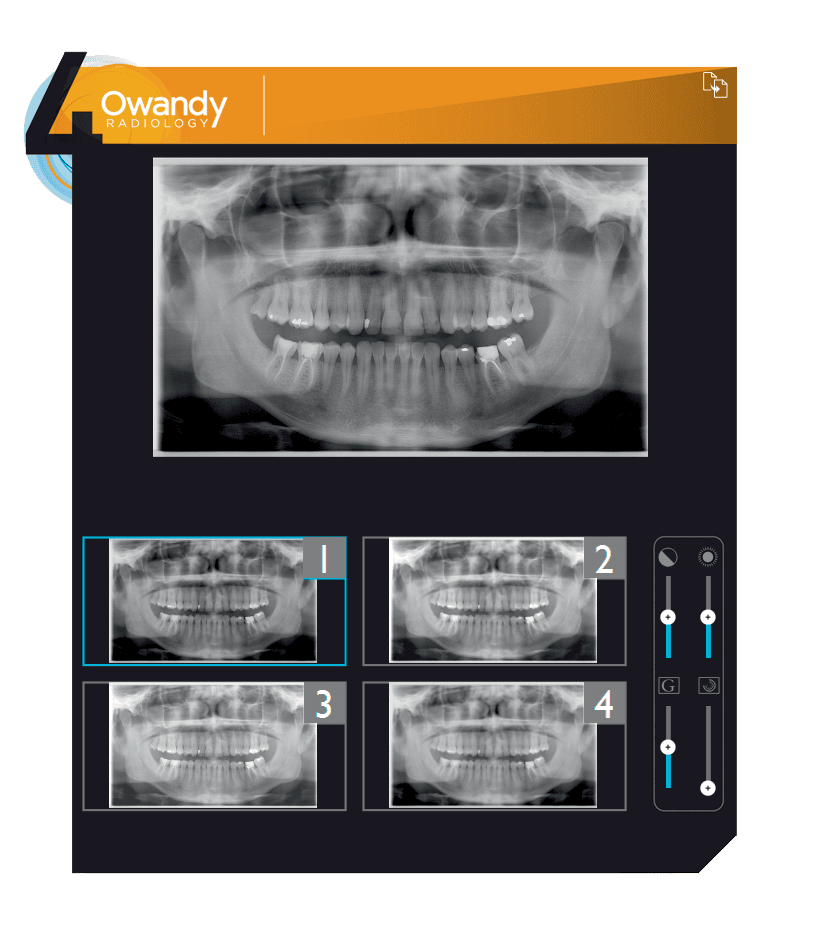

QuickVision

QuickVision is software designed for dental surgeries, and comprises a patient database, an imaging module and an odontogram.

With QuickVision, users can carry out all imaging functions that a dental surgery is required to do on a daily basis: creating and viewing images, and accessing tools to enhance, measure, zoom in on and annotate images, as well as sharing data and images.